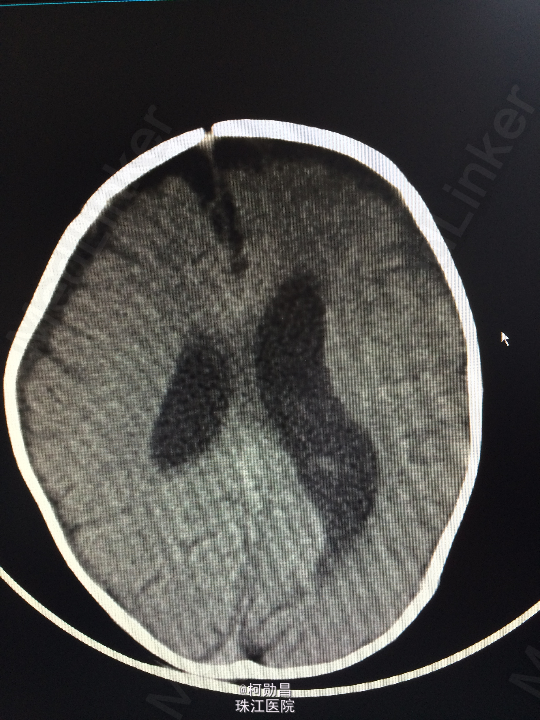

主诉:发热10天,抽搐3天 病史:患儿出生后8个月,因“发热10天,抽搐3天”入院,入院时体温39.3℃,神志不清,反应差。四肢肌张力增高,以双上肢肌力增高明显。病理征未引出。

查体:神志不清,四肢肌力增高 辅助检查:头颅CT提示脑积水并脑脊液外渗,幕上脑室扩张,右侧额颞叶硬膜下脑脊

诊断:化脓性脑膜炎伴脑积水 处理:予内科抗感染治疗,后行脑室腹腔引流术。